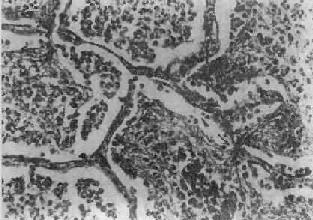

图9-19 支气管肺炎 图中见灶状实变的肺组织,肺泡内充满以中性粒细胞为主的炎性渗出物;病灶中有发炎的细支气管 【并发症】 小叶性肺炎发生并发症的危险性比大叶性肺炎大得多。可并发心力衰竭、呼吸衰竭、脓毒败血症、肺脓肿及脓胸等。支气管破坏较重且病程较长者,可导致支气管扩张。 【临床病理联系】 因小叶性肺炎多为其他疾病的并发症,其临床症状常为原发性疾病所掩盖。由于支气管粘膜的炎症刺激而引起咳嗽,痰呈粘液脓性。因病变常呈灶性散布,肺实变体征一般不明显。病变区细支管和肺泡内含有渗出物,听诊可闻湿啰音。X线检查,可见肺野内散在不规则小片状或斑点状模糊阴影。本病发现及时,治疗得当,肺内渗出物可完全吸收而痊愈。但在幼儿,年老体弱者,特别是并发于其他严重疾病时,预后大多不良。 (二)病毒性肺炎 病毒性肺炎(viral pneumonia)常常是因上呼吸道病毒感染向下蔓延所致。患者多为儿童,症状轻、重不等,但婴幼儿和老年患者病情较重。一般多为散发,偶可酿成流行。引起肺炎的病毒种类较多,常见的是流感病毒、还有呼吸道合胞病毒、腺病毒、副流感病毒、麻疹病毒、巨细胞病毒等等,也可由一种以上病毒混合感染并可继发细菌感染。病毒性肺炎的病情、病变类型及其严重程度常有很大差别。 【病理变化】 早期或轻型病毒性肺炎表现为间质性肺炎,炎症从支气管、细支气管开始,沿肺间质发展,支气管、细支气管壁及其周围、小叶间隔以及肺泡壁等肺间质充血、水肿,有一些淋巴细胞和单核细胞浸润,肺泡壁明显增宽(图9-20)。肺泡腔内一般无渗出物或仅有少量浆液。病变较重者,肺泡也可受累,出现由浆液、少量纤维蛋白、红细胞及巨噬细胞组成的炎性渗出物,甚至可发生组织坏死。有些病毒性肺炎(如流感病毒肺炎,麻疹病毒肺炎、腺病毒肺炎等)肺泡腔内渗出较明显,渗出物浓缩凝结成一层红染的膜样物贴附于肺泡内表面,即透明膜形成。支气管上皮的肺泡上皮也可增生,甚至形成多核巨细胞。麻疹病毒肺炎的病变特点为在间质性肺炎的基础上,肺泡壁上有透明膜形成,并有较多的多核巨细胞(巨细胞肺炎),在增生的上皮细胞和多核巨细胞的胞浆内和胞核内可检见病毒包含体。病毒包含体常呈球形,约红细胞大小,呈嗜酸性染色,均质或细颗粒状,其周围常有一清晰的透明晕。其他一些病毒性肺炎也可在增生的支气管上皮、支气管粘液腺上皮或肺泡上皮细胞内检见病毒包含体。如腺病毒肺炎可在增生的上皮细胞核内(图9-21),呼吸道合胞病毒肺炎可在增生的上皮细胞胞浆内,巨细胞病毒肺炎也可在增生的上皮细胞核内检见病毒包含体。检见包含体是病理组织学诊断病毒性肺炎的重要依据。

图9-17 肺肉质变 肺泡腔内炎性渗出物已被结缔组织所替代 (2)肺脓肿及脓胸或脓气胸:多见于由金黄色葡萄球菌引起的肺炎。 (3)纤维素性胸膜炎:是肺内炎症直接侵犯胸膜的结果。 (4)败血症或脓毒败血症:见于严重感染时,细菌侵入血流繁殖所致。 (5)感染性休克:严重的肺炎链球菌或金黄色葡萄球菌感染引起严重的毒血症时可发生休克,称休克型或中毒性肺炎,病死率较高。 【临床病理联系】 疾病发展过程中病变表现不一,临床体征也不相同。疾病早期时,主要病变是肺泡腔内浆液渗出,听诊可闻湿啰音,X线检查仅见肺纹理增深。肺实变时,由于肺泡膜面积减少,可出现肺泡通气和血流比例失调而影响换气功能,使肺静脉血不能充分氧合,患者乃出现紫绀或呼吸困难。渗出物中红细胞为肺泡巨噬细胞吞噬,崩解后形成含铁血黄素混入痰中,使痰呈铁锈色。痰中可检出“心衰细胞”。肺实变的体征是,肺泡呼吸音减弱或消失,出现支气管呼吸音,语音震颤增强,叩诊呈浊音。因常并发纤维素性胸膜炎,患者有胸痛,听诊可闻胸膜摩擦音。X线检查,可见大叶性或段性分布的均匀性密度增高阴影。病变消散时,渗出物溶解液化,肺部可闻及捻发音,X线表现为散在不均匀片状阴影,约在2~3周后阴影方完全消散。抗生素治疗,可缩短病程,减轻病变,合并症也大为减少。 2.小叶性肺炎 小叶性肺炎(lobular pneumonia)主要由化脓菌感染引起,病变起始于细支气管,并向周围或末梢肺组织发展,形成以肺小叶为单位、呈灶状散布的肺化脓性炎。因其病变以支气管为中心故又称支气管肺炎(bronchopneumonia)。主要发生于小儿和年老体弱者。 【病因和发病机制】 小叶性肺炎主要由细菌感染引起,常见的致病菌有葡萄球菌、链球菌、肺炎球菌、流感嗜血杆菌、绿脓杆菌和大肠杆菌等。这些细菌通常是口腔或上呼吸道内致病力较弱的常驻寄生菌,往往在某些诱因影响下,如患传染病、营养不良、恶病质、慢性心力衰竭、昏迷、麻醉、手术后等,使机体抵抗力下降,呼吸系统的防御功能受损,细菌得以入侵、繁殖,发挥致病作用,引起支气管肺炎。因此,支气管肺炎常是某些疾病的并发症,如所谓麻疹后肺炎、手术后肺炎、吸入性肺炎、坠积性肺炎等等。 【病理变化】 小叶性肺炎的病变特征是肺组织内散布一些以细支气管为中心的化脓性炎症病灶。常散布于两肺各叶,尤以背侧和下叶病灶较多。病灶大小不等,直径多在1cm左右(相当于肺小叶范围),形状不规则,色暗红或带黄色(图9-18)。严重者,病灶互相融合甚或累及全叶,形成融合性支气管肺炎(confluent bronchopneumonia)。镜下,病灶中支气管、细支气及其周围的肺泡腔内流满脓性渗出物,纤维蛋白一般较少(图9-19)。病灶周围肺组织充血,可有浆液渗出、肺泡过度扩张等变化。由于病变发展阶段的不同,各病灶的病变表现和严重程度亦不一致。有些病灶完全化脓,支气管和肺组织遭破坏,而另一些病灶内则可仅见浆液性渗出,有的还停留于细支气管及其周围炎阶段。